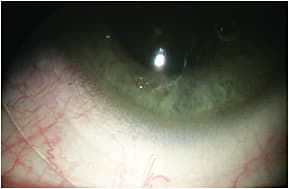

- Presence of Sectorial Blanching On a highly toric or asymmetric sclera, the spherical SL will exhibit lens touch at the flattest meridian/quadrant and lift-off in the steepest one. Excessive bearing will compress the conjunctival vessels, resulting in sectorial blanching (Figure 2). Sectorial blanching in the horizontal meridian means that the sclera has with-the-rule toricity. It may also appear only in one quadrant, typically the flattest. At lens removal, there will be a rebound hyperemia in the area in which the landing zone restricted the blood vessels. The amount of blanching is directly proportional to the scleral toricity. When blanching occurs, a toric lens or a quadrant-specific design is indicated. Blanching may appear in different areas of the landing zone: in the inner area near the limbal zone (Figure 3) or in the outer area near the lens edge.

- Removing the Lens Fluorescein instillation at lens removal may reveal sectorial conjunctival staining. This appears when the lens edge is too steep in a specific area, resulting in impingement into the conjunctiva (Figure 6). When the sclera has with-the-rule toricity, impingement will occur in the horizontal meridian. When the impingement appears only in one quadrant, this indicates that the sclera is asymmetric. In this case, flattening the lens edge in the area of impingement is needed. Sectorial impingement and blanching may occur together and are more likely caused by a lens that is steep in a specific zone (Figure 3).